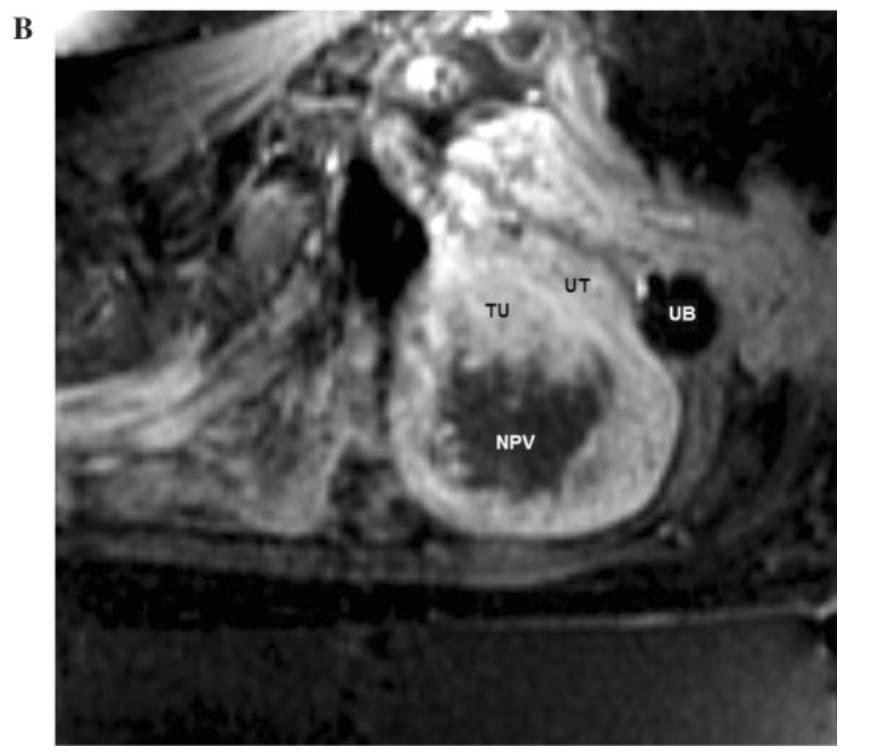

B:治疗前的核磁共振显像,NPV:(磁波治疗后被消融的)无灌注体积

磁波治疗过程顺利,治疗后有33立方厘米的病灶被消融,不再有血流灌注(NPV),